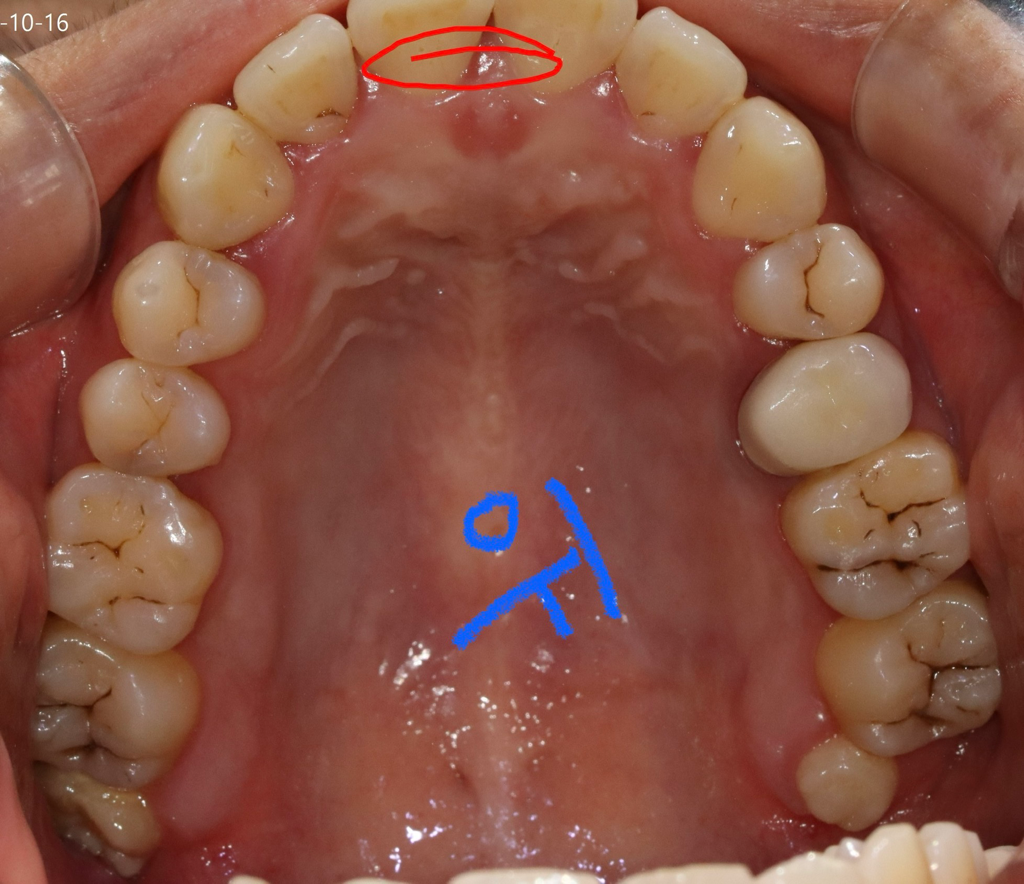

사진만 가지고는 정확한 충치 판별이 어렵습니다. 레진은 대략 10~20만원, 인레이는 30~40만원 정도 입니다.

충치 범위가 넓어서 인레이를 해야될 가능성이 높아 보입니다. 인레이 가격은 재료에 따라 다릅니다. 대략 25-40만원까지 다양합니다.